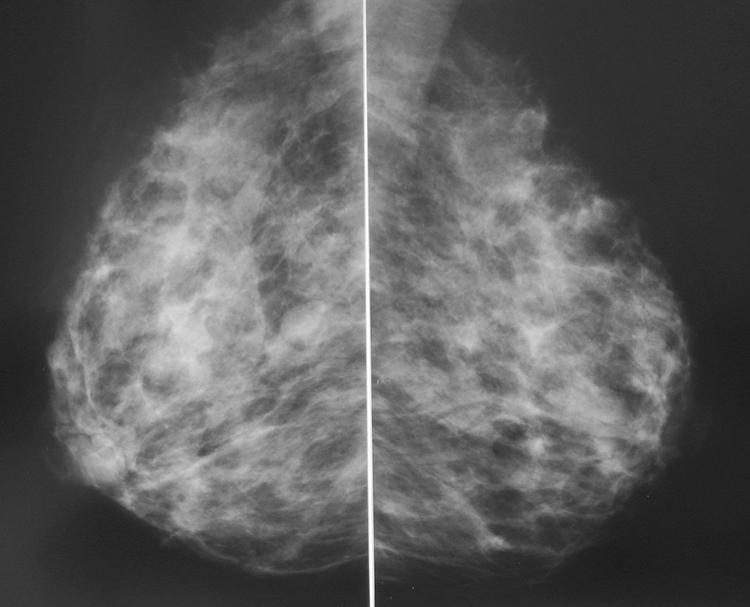

Аномалии молочной железы: медицинские примеры и визуализация